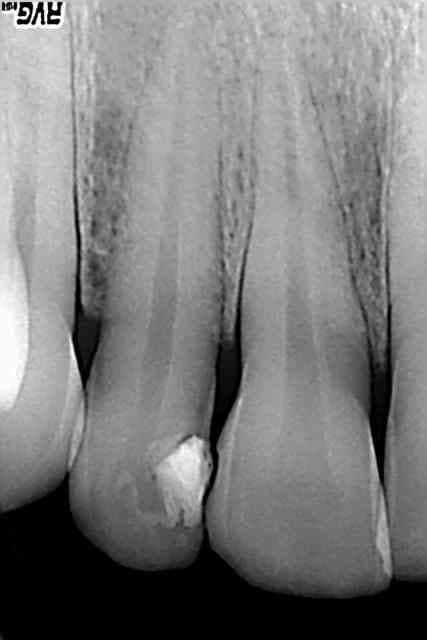

tiens, pour obtenir ce genre d'image, y a pas besoin de gutta tueuse de microbe. conclusion faut plus se préoccuper de la préparation que de l'obturation.